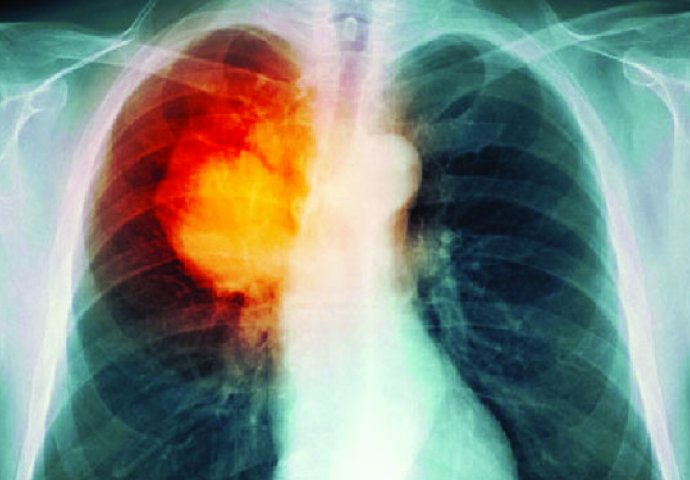

Dugo vremena ljudi su se pitali zašto neki pušači i pored nezdravog načina života dožive dugu starost i u čemu se krije tajna.

Naime, američki naučnici su otkrili da neki pušači dožive duboku starost iako puše, a to mogu zahvaliti – genima.

Do ovog rezultata naučnici su došli tako što su proučavali pušače koji dugo žive i primijetili su da im je jedna stvar zajednička, a to su geni dugovječnosti.

Njima ti geni omogućavaju da budu otporniji na štetne tvari iz cigareta, ali i uopšteno na ostala zagađenja oko nas. Oni koji imaju takve gene imaju ujedno i 11 posto manje šanse da dobiju neku vrstu raka.